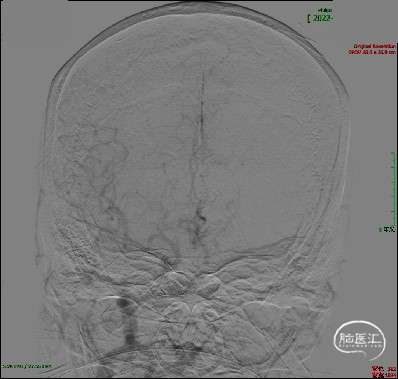

急诊DSA:主动脉弓造影提示LICA闭塞,RICA代偿差。

急诊DSA:LICA闭塞,LICA起始部次全闭塞。

急诊DSA:微导管于LICA-C2段造影见血栓近端所在,明确患者为LICA起始段次全闭塞合并远端栓塞的串联病变。

双重负压抽吸下回撤取栓支架,造影见mTICI 3级再通。